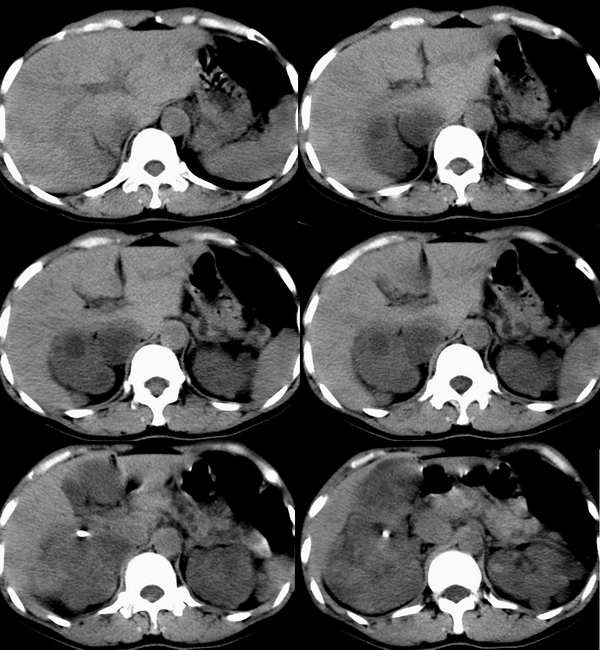

动脉期

右肾体积增大,形态失常,其内可见多发低密度影,增强后动脉期病灶实质明显强化,低密度区未见强化,静脉期病灶呈等密度,考虑右肾癌,左肾多发囊肿,多囊胰

右肾体积增大,形态失常,其内可见多发低密度影,增强后动脉期病灶实质明显强化,低密度区未见强化,静脉期病灶呈等密度.